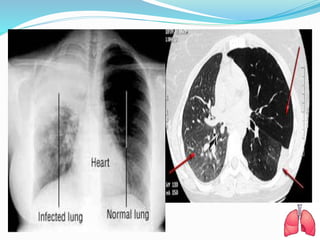

DIAGNOSTIC EVALUATION

 Physical examination.

 Chest X-ray.

 CT Scan thorax.